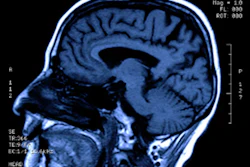

Functional MRI (fMRI) indicates that 25% of unresponsive brain injury patients can still perform cognitive tasks, according to a study published August 14 in the New England Journal of Medicine.

The investigators conducted a study that included clinical, behavioral, and task-based fMRI and EEG data from 353 adults. Of these, 241 were in coma, vegetative, or minimally conscious states. They assessed these patients' responses to commands and compared them to participants with observable responses to commands using the Coma Recovery Scale-Revised (CRS-R); information from fMRI or EEG only was available for 65% of the participants, while information from both fMRI and EEG were available for 35%. The median patient age was 37.9 years, and the median time between brain injury and CRS-R assessment was 7.9 months (although 25% of patients were assessed within 28 days after sustaining the injury).

The authors found cognitive motor dissociation in 25% of patients without observable response to commands; 11 of these were evaluated with fMRI only, 13 with EEG only, and 36 with both exams. The phenomenon was associated with younger patients with cognitive motor dissociation compared with those without it (30.5 years vs. 45.3 years) and longer time since injury (10.7 months vs. 4.3 months). Bodien and colleagues noted that the percentage of participants with cognitive motor dissociation was five to 10 percentage points higher in their study than in previous studies.

Standardized behavioral evaluation "remains the reference standard for detecting a response to commands at the bedside, the use of task-based fMRI and EEG can improve detection, and the use of both imaging techniques appears to be a more sensitive approach than the use of one of the techniques alone," the group explained, but identifying cognitive motor dissociation is key to better patient care.